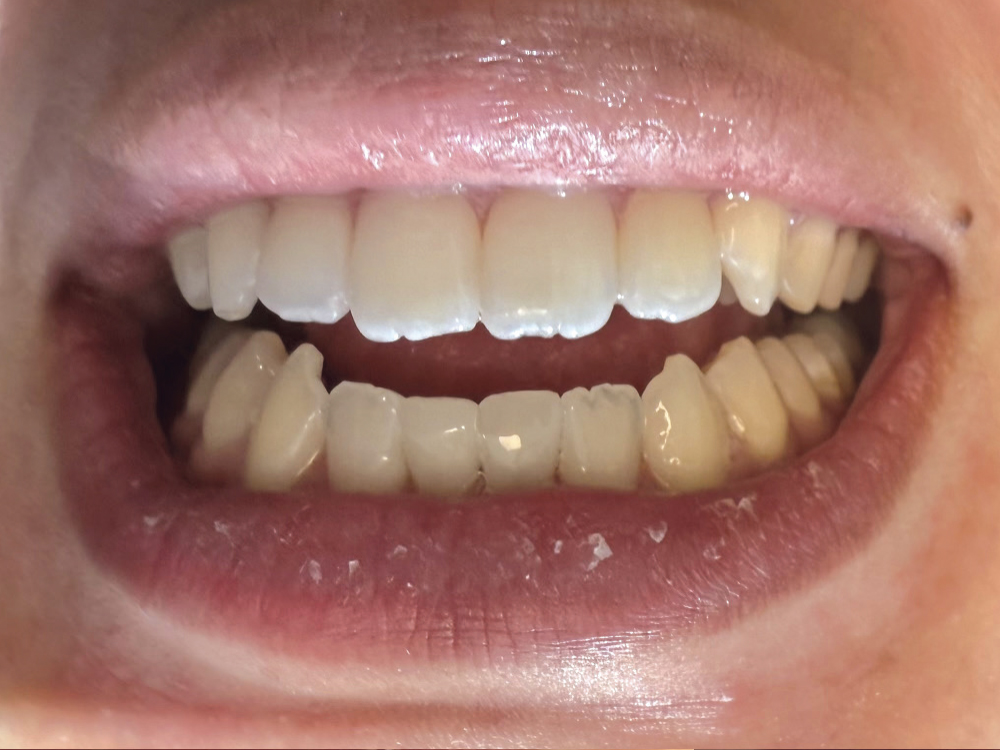

Recently, I had a young patient with two retained primary incisors on the lower arch — small, gray and highly visible. She had been quoted over $10,000 for implants elsewhere, which wasn’t feasible for her. I offered a same-day solution using milled composite crowns. We prepped conservatively, milled two units with CAMouflage® NOW Milling Blocks in under 15 minutes, and delivered them that hour. The transformation was stunning — and the experience was life-changing for her. She told me later that she originally didn’t believe me when I said we could fix it in one appointment. Seeing her smile without hesitation was a moment I won’t forget.

Before Crowns

After Crowns

Retained primary teeth O and P were crowned with composite crowns milled out of CAMouflage® NOW Milling Blocks in about 7 minutes. In less than an hour, this patient was able to smile like never before.